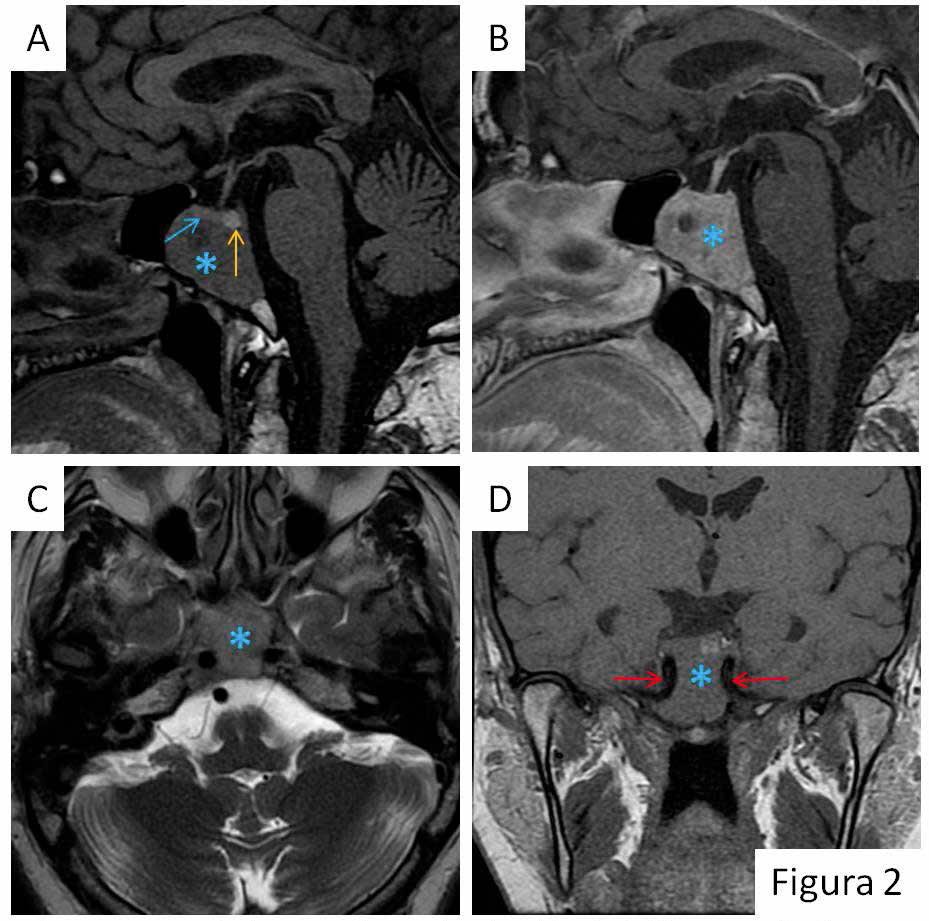

El paciente refería disminución del apetito sexual y disfunción eréctil de 10 años de evolución, con empeoramiento en los últimos 5 años, sin alteraciones visuales ni otra sintomatología asociada. Ante la sospecha de prolactinoma se inició tratamiento con cabergolina 0.5 mg hasta alcanzar la dosis de 1 mg dos veces por semana y se completó el estudio con pruebas de imagen (Figuras 1 y 2) confirmándose la presencia de un macroadenoma hipofisario ectópico. Tras cuatro meses de tratamiento, el paciente refirió clara mejoría de la clínica con normalización de los niveles de hormonas (prolactina basal: 15.5 ng/mL y testosterona total: 2.630 ng/mL).

En la RM de control realizada al año de tratamiento se evidencia discreta disminución de la intensidad de la masa y estabilización del tamaño.

La TC (tomografía computerizada) y la RM (resonancia magnética) pueden ser de utilidad en el diagnóstico preoperatorio, aunque supone un reto puesto que al ser una patología tan poco frecuente, es difícil incluir esta patología en el diagnóstico diferencial de rutina1.

Este tipo de lesiones se ven isointensas respecto a la sustancia gris cerebral en las secuencias T1 con captación heterogénea tras la administración de contraste.

Aunque no se evidencia un claro plano de separación con la hipófisis, la cual es de morfología y tamaño normales, existen diferencias en la intensidad de señal y debido al patrón de crecimiento en sentido caudal (en condiciones normales los macroadenomas tienden a crecer hacia la región supraselar que es donde existe menos resistencia), así como por su localización clival, a pesar del tamaño y de no tener la anatomía patológica se ha diagnosticado de macroprolactinoma clival ectópico.